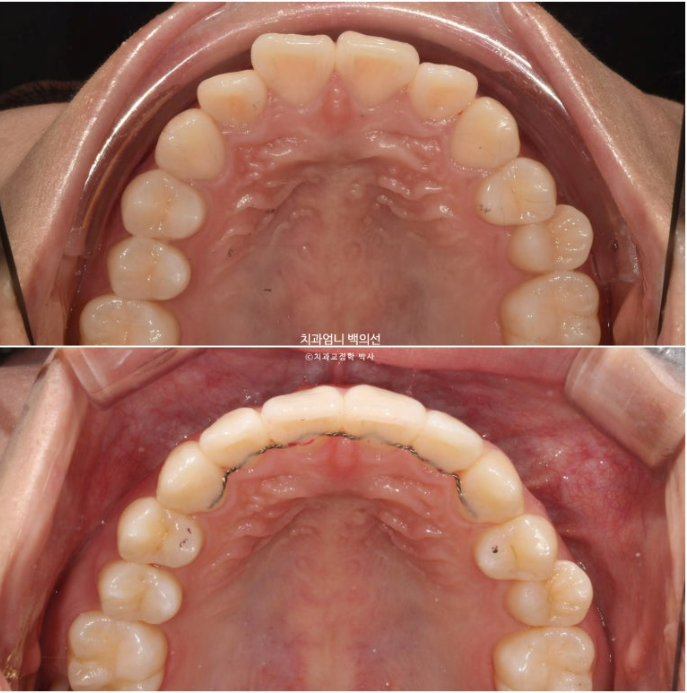

치료시작 9개월째 모습입니다.

앞니 사이 미세한 틈을 없애기 위한 파워체인 고무줄을 걸고

사진에 보이는 고리끼리는 환자분이 스스로 뺐다 꼈다 하는 고무줄을 걸며 중심선과 좌우 교합까지 맞춥니다.

MTA 장치는 송곳니부터 송곳니까지 앞니에만 붙여서 배열을 진행했고 나머지 작은어금니와 큰어금니는 움직이지 않았습니다.

유지장치까지 붙은 모습입니다.

23.12~24.09

가지런한 앞니 배열과 철사 유지장치